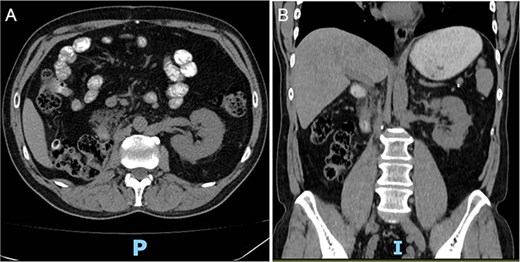

Follow-up CT imaging (Fig. 3A–D) showed a reduction in both the tumor and thrombus size, leading to the classification of the thrombus from Stage IV to Stage III according to the Mayo Clinic classification.

(A–D) Abdominopelvic contrast-enhanced computed tomography post-neoadjuvant therapy showed a significant reduction in tumor size and the involvement of the thrombus in the azygos vein.

Based on these post-treatment findings, a joint decision with Urology was made to avoid a thoraco-phreno-laparotomy, opting instead for an extended supra-infraumbilical right subcostal laparotomy.